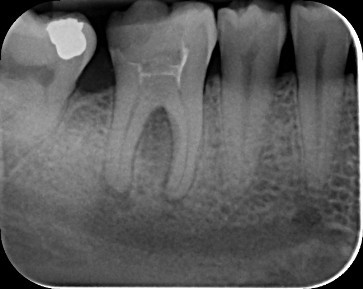

Case 2: Root canal treatment LR6